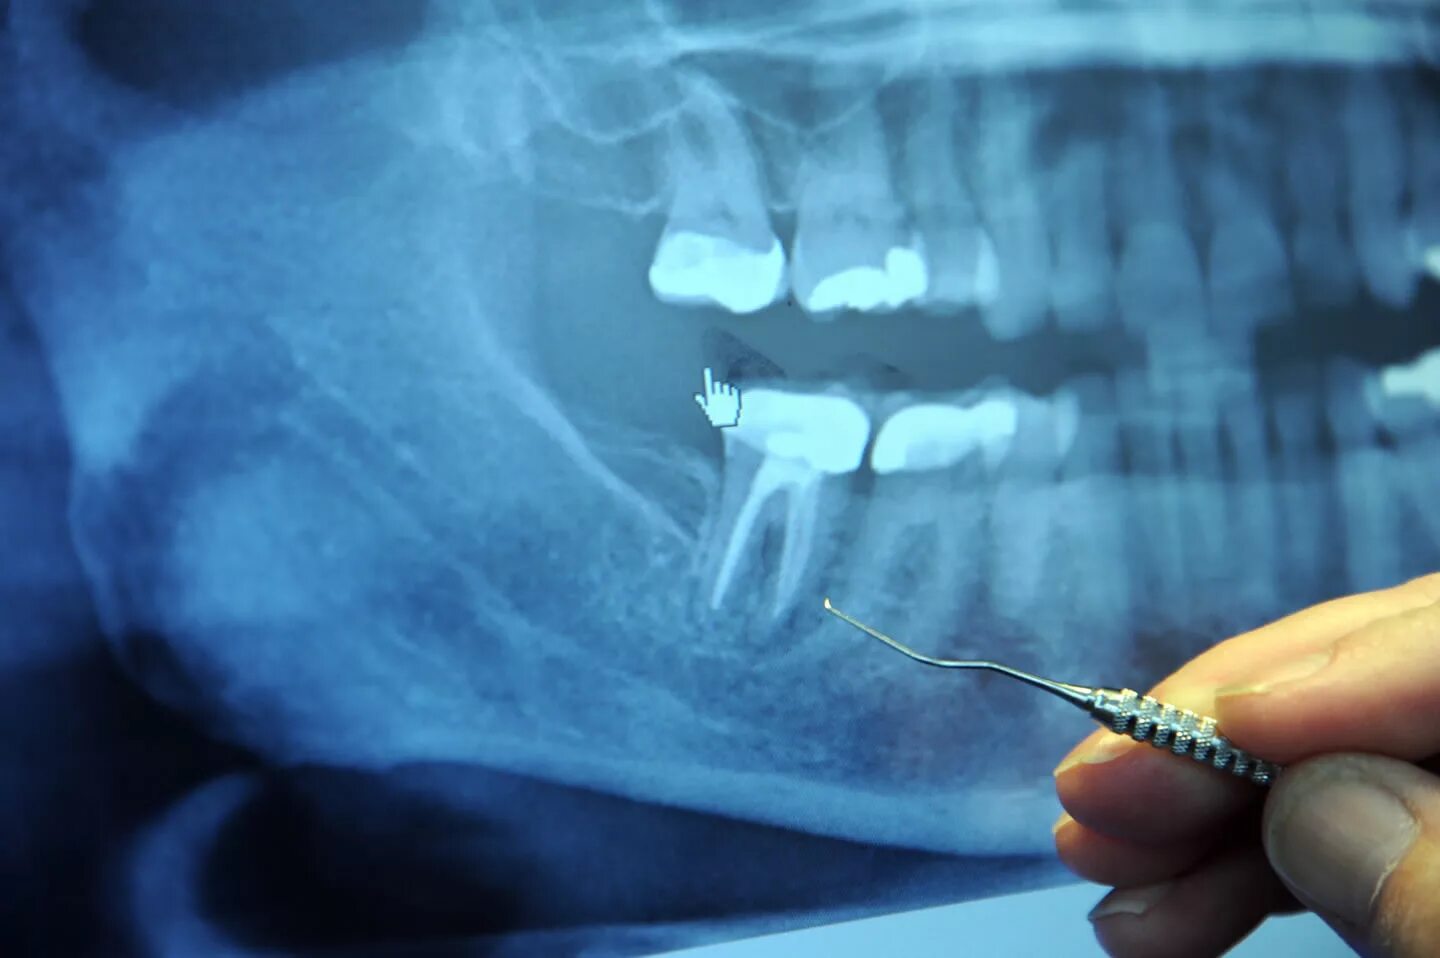

Зуб с удаленным нервом